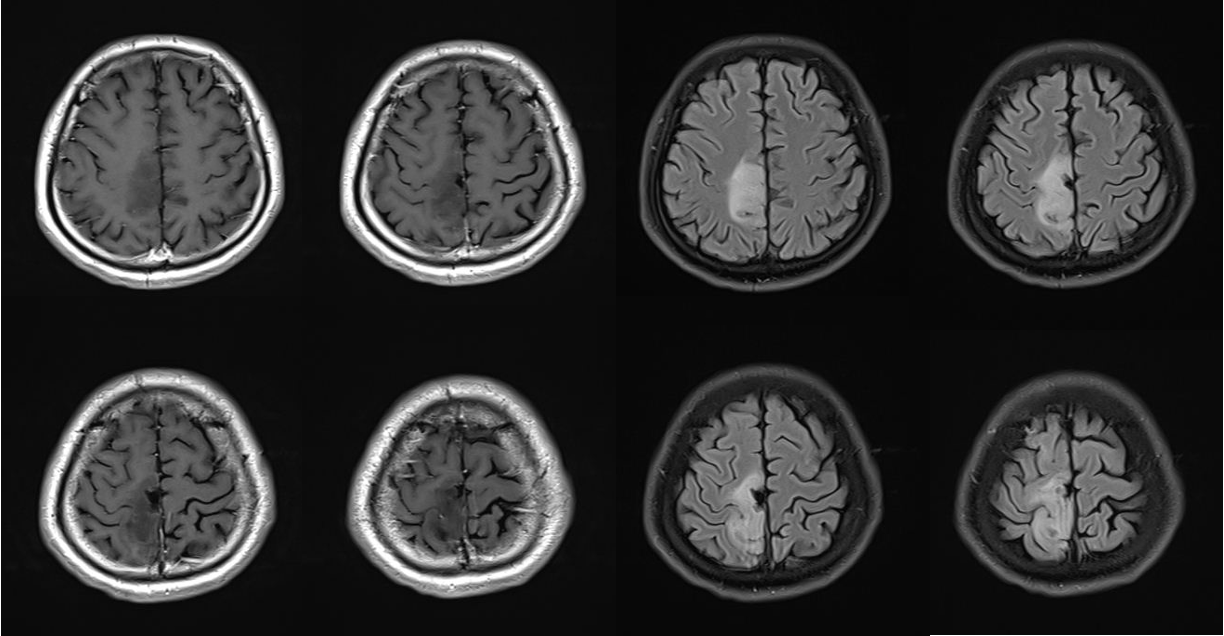

今年32岁的王先生在2018年因为癫痫发作,发现右侧额顶叶占位病变,因为肿瘤累及运动功能区,当地医院进行了肿瘤部分切除。术后病理诊断为弥漫型星形细胞瘤(WHOII级,IDH突变型)。手术后,患者出现左下肢活动受限,偶有癫痫发作。2022年10月开始,王先生癫痫发作情况有所加重,在当地检查发现肿瘤复发,今年,他来到北京天坛医院神经外科就诊。

为了确保万无一失,医疗团队和工程技术人员团队一起,为王先生进行了充分的术前准备,通过任务态功能磁共振(t-fMRI)和纤维束成像(DTI)技术确定运动区和神经传导束的位置及与肿瘤的毗邻关系,反复讨论确定神经导航计划、不同剂量的双光纤消融,以及激光光纤置入路径和治疗靶点等。

“在手术中,磁共振成像实时监测可以让我们实时观看消融效果,进行及时的反馈和调整,既满足安全性,又可以达到最佳的效果,手术时间比传统的开颅手术缩短了至少一半。”周大彪说。手术后,王先生很快清醒,自述原本活动受限的左下肢比手术前轻松许多;大约8小时后CT检查未见颅内出血等情况;术后第三天,北京天坛医院神经外科学中心主任江涛和医疗团队一起专门查看王先生情况,发现他左下肢远端肌力恢复良好,预示神经功能恢复的可能性很大,江涛建议密切随访观察远期效果,患者头部微小伤口无缝合线、愈合良好,无颅内感染表现;手术一周后,王先生复查磁共振后顺利出院。